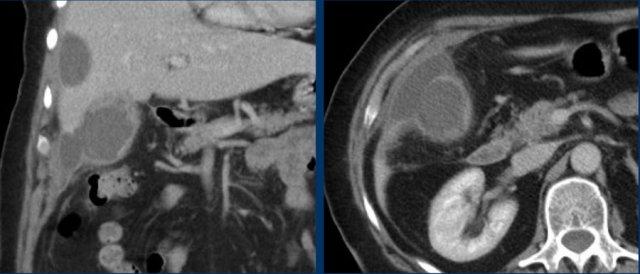

CT trong viêm túi mật cấp

CT có thể rất hữu ích trong các trường hợp siêu âm không cho kết quả chẩn đoán.

Đây là hình ảnh của một bệnh nhân béo phì với đau hạ sườn phải cấp tính trong 6 giờ. CRP 2.

Siêu âm cho thấy túi mật lớn có bùn mật, không quan sát thấy sỏi.

Việc ấn vào túi mật không đáng tin cậy do vị trí cao dưới cung sườn phải.

Không có bất thường siêu âm nào khác.

CT thực hiện cùng ngày cho thấy túi mật lớn với chỉ những thay đổi quanh túi mật kín đáo và không có nguyên nhân nào khác giải thích cho các triệu chứng.

Ngày hôm sau CRP là 105 và CT không tiêm thuốc cản quang lặp lại cho thấy quầng mờ xung quanh túi mật.

Phẫu thuật tiếp theo xác nhận viêm túi mật cấp giai đoạn sớm do sỏi nhỏ trong ống túi mật.